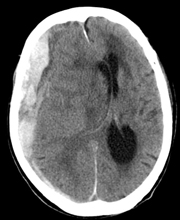

急性硬膜外血種

頭蓋骨と硬膜の間にできた血種を急性硬膜外血種といいます。主な出血源は、頭蓋骨骨折によって損傷された中硬膜動脈や骨折部の骨であり、多くの場合、頭蓋骨骨折を伴い外力を受けた直下に生じます。

一時的に意識がはっきりした後に意識障害を認めることが多く、頭痛や嘔吐、瞳孔不同(左右の瞳孔の大きさが異なる状態)や運動麻痺をみることもあります。

基本的には手術によって血腫を除去します。意識障害が軽度な場合は、手術をせずに保存的に治療することもあります。外傷による頭蓋内出血のなかでは、最も予後(経過)はよいといわれています。